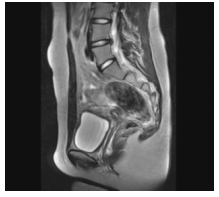

A imagem a seguir representa